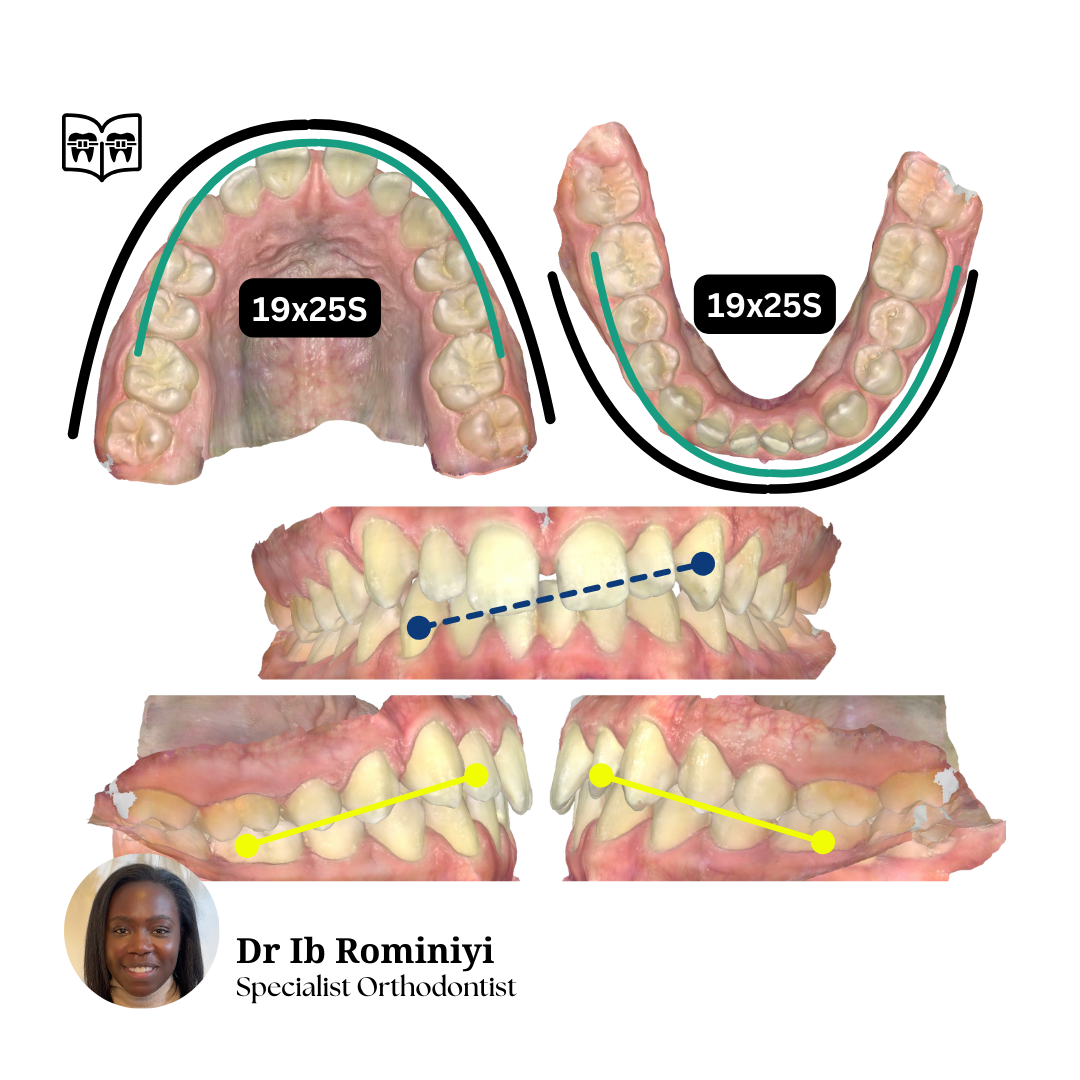

M E N T O R I N G M O M E N T

#1

Dentist's Question: I'm currently in upper 19x25N, lower 18x25S and the lateral open bites and centrelines are getting worse.

How would you improve the bite?

What mechanics & archwires would you use from here?